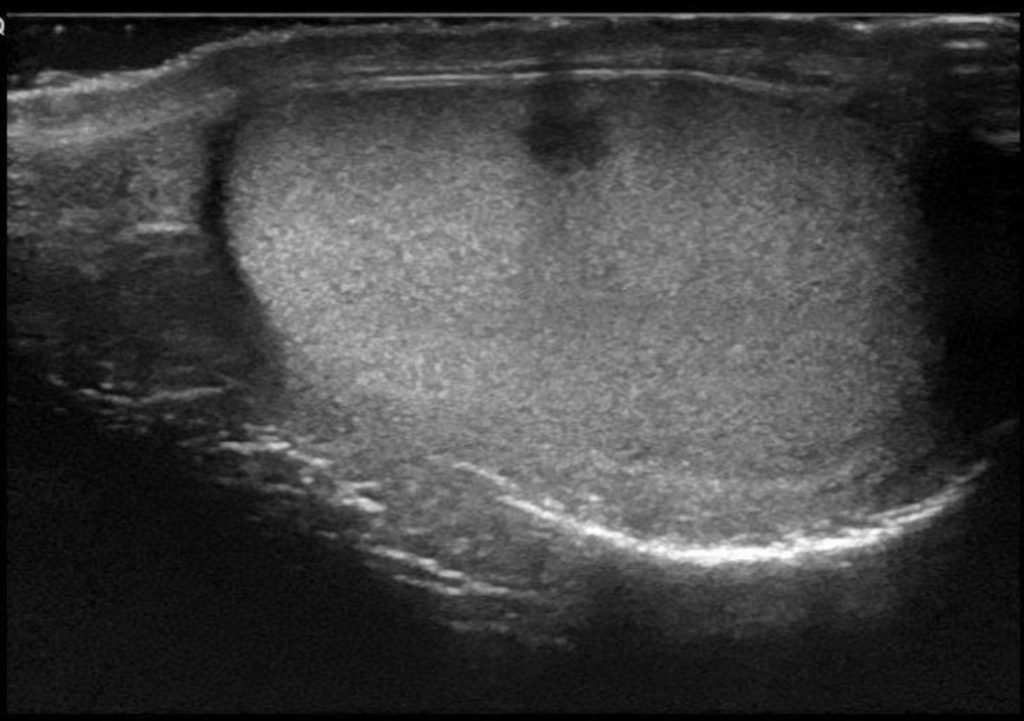

The only obvious symptom is the absence of one or both testes in the scrotum. In 80% of cases, the testicles, which cannot be seen visually, are palpable, but in the remaining 20%, they contract excessively and cannot be touched. Even so, it should be noted that most are temporary and the problem will resolve on its own after 6 months.